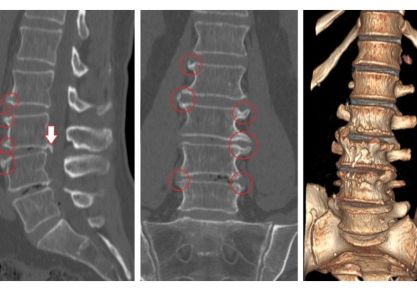

Данное поражение суставов является самым распространенным среди взрослого населения. Оно развивается у любого человека, независимо от возраста (может появляться не только у пожилых людей, но также и у молодежи), пола. Это целый комплекс дистрофических поражений хрящевой ткани. Болезнь имеет характерную особенность — она поражает чаще всего межпозвоночные диски.

Чаще всего это заболевание считается главной причиной появления болевого синдрома в спине. Впервые почувствовать развитие болезни можно уже в 20 лет. Далее, она очень быстро прогрессирует и становится только хуже. Боль является следствием того, что хрящ, который обеспечивает амортизационные свойства позвоночника, истончается. Диски сильно прижимаются друг к другу и поддаются трению, доставляя человеку дискомфорт.

1. Остеохондроз поясничного отдела (встречается очень часто).

2. Остеохондроз грудного отдела.

3. Остеохондроз шейного отдела.